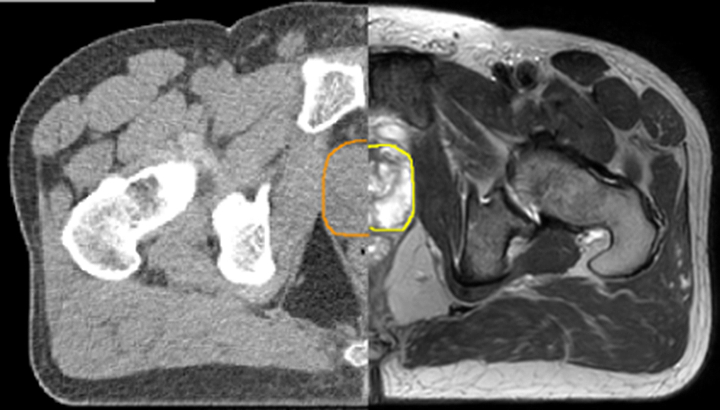

With its superior soft tissue contrast compared to CT, MRI offers exquisite visualization of tumor boundaries and proximity to nearby critical structures.

The ability to tune contrasts can provide even more valuable information about tumor characteristics and tumor extent to facilitate enhanced delineation, and also provides possibilities for dose boosting strategies.

In addition to anatomical imaging, MRI offers the ability to obtain functional information that is beneficial for tumor detection and delineation, and for response monitoring.

Diffusion-weighted imaging (DWI) for example depicts areas of high signal intensity in soft tissues that are indicative of the restricted water mobility (i.e., diffusion) of a tumor and can also be used to identify lymph nodes. Changes in the tissue’s or lesion’s apparent diffusion coefficient (ADC) can provide insights that help predict the tumor’s response to radiotherapy.